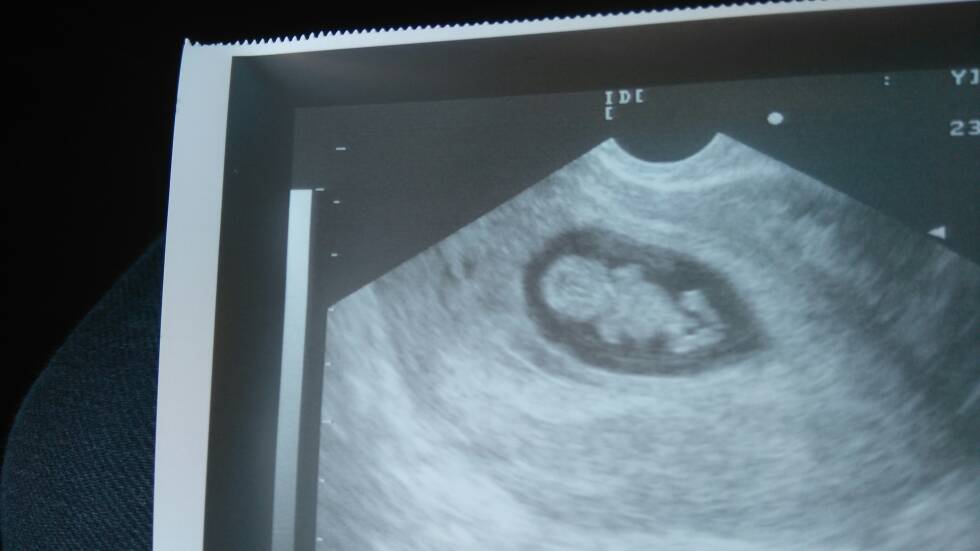

Jestem tu nowa...ostatnia miesiaczka 21.08 wiec 6t i 2d ciazy...wg uaag wczorajszego wczesna ciaza...

I moze blizniacza...niech ktoras mi powie ze tez tak ma lub miala [emoji18]

Jeat niestety mozliwosc wchloniecia sie drugiego pecherzyka ale mam nadzieje ze jak sa 2 to beda i 2 dzidzie...

Nastepna wizyta 19.10 i sie okaze czy bedzie 1 czy 2 dzieci